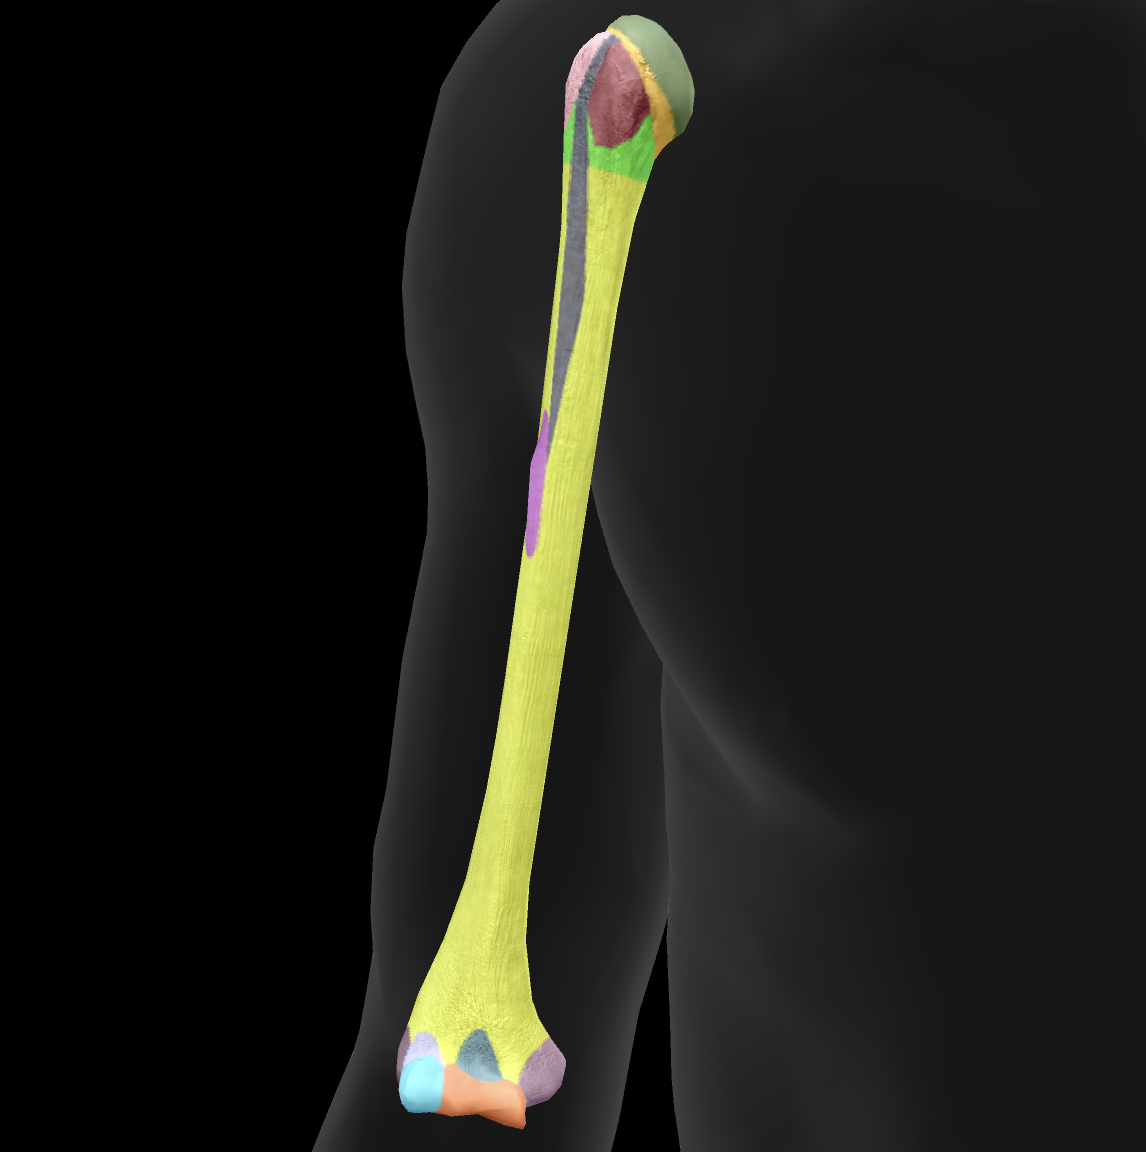

What bone is this?

ulna

What is this boney landmark?

trochlea notch

What is this boney landmark?

coronoid process

What is this boney landmark?

radial notch

What is this boney landmark?

ulnar tuberosity

What is this boney landmark?

shaft

What is this boney landmark?

head

What is this boney landmark?

styloid process

What is this boney landmark?

olecranon process

What is this bone?

radius

What is this boney landmark?

head

What is this boney landmark?

neck

What is this boney landmark?

radial tuberosity

What is this boney landmark?

shaft

What is this boney landmark?

radial styloid process

What is this boney landmark?

ulnar notch

What is this boney landmark?

lister’s tubercle